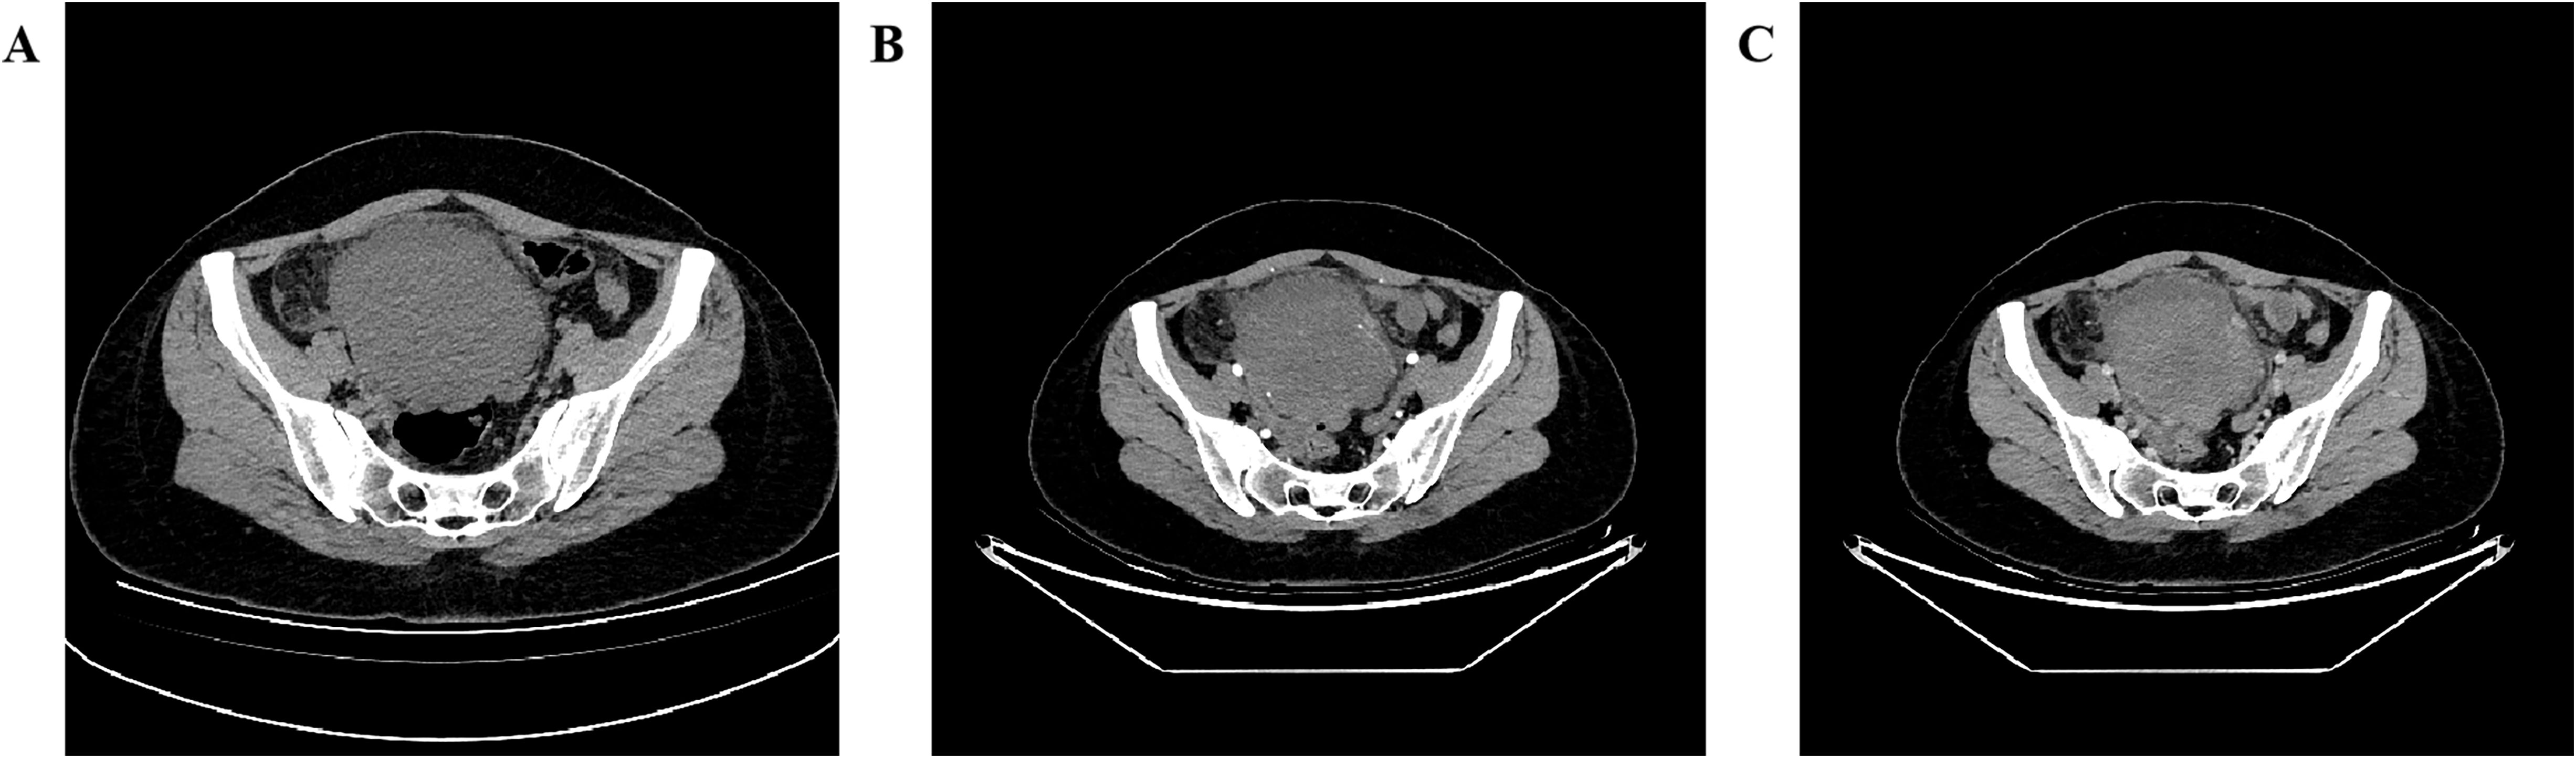

A 27-year-old woman came to the doctor because of intermittent pain in the lower abdomen for more than 1 month and fever 1 day ago. During this period, the symptoms were relieved after oral medication (details are unknown). A week ago, there was no obvious inducement for migratory abdominal pain, which transferred from the umbilicus to the right lower abdomen, and the pain worsened after changing the body position. Physical examination: obvious tenderness in the right lower abdomen, no rebound pain and muscle tension. A mass about 10 cm × 8 cm in size was palpable in the pelvic cavity, with unclear boundaries and inactive adhesions to the pelvic cavity. Blood routine examination: white blood cell count 13.1 (109/L)↑, neutrophil count 10.9 (109/L)↑, monocyte count 1.3 (109/L)↑, neutrophil ratio 82.7 (%)↑, lymphocyte ratio 8.7 (%)↓, acidophage ratio 0.0 (%)↓, high-sensitivity C-reactive protein 140.2 mg/L↑. Ultrasound examination: A hypoechoic mass with a size of about 11 cm × 8 cm ×10 cm was found in the pelvic cavity, The internal echo is uneven, with no obvious liquefied areas or calcification foci. The mass has a clear boundary and a relatively regular shape; CDFI: punctate blood flow signals were seen in it, PW: PS: 20.4 cm/s, S/D: 2.3, RI: 0.57. Two circular hypoechoic nodules were found in the right abdominal cavity, the larger one was about 13 mm × 13 mm (Figure 1). Ultrasound suggests: hypoechoic mass in pelvic cavity, considering neoplastic lesions, the source cannot be defined; Enlarged lymph nodes in the right abdominal cavity. CT examination revealed a slightly higher density mass in the pelvic cavity, about 10 cm × 9 cm in size, with a CT value of about 25HU. The edge was under smooth and the lesion enhancement was uneven. The local enhancement of the upper edge was obvious, and the overall enhancement was mild. The branch vessels of the superior mesenteric artery passed through it, the space around the lesion was blurred, and multiple enlarged lymph node shadows were seen. The mass is located above the bladder, anterior and superior to the uterus and closely adherent to it, with indistinct boundaries from the right adnexal region broussonetia papyrifera. The sigmoid colon is displaced cephalad and posteriorly (Figures 2, 3). Between the mass and the bladder, compressed small bowel loops can be visualized. CT suggested: pelvic space-occupying lesions, adjacent multiple lymph nodes enlarged, and neoplastic lesions were considered. The patient underwent surgical treatment. During the operation, a huge mass was found in the ileocecal part, about 15 cm × 14 cm × 13 cm in size. The tumor was necrotic, and pus moss attached to the surface. The lesion involved part of the ascending colon and terminal ileum, and about 200ml of purulent exudate was seen in the abdominal cavity. Finally, the mass was completely removed, and part of the intestinal tube and omentum were removed. Pathological examination: naked eyes: a mass can be seen on the serosal surface of one side of the intestinal tube, which is closely connected with the intestinal tube, It has a size of 12 cm × 12 cm × 10 cm. The capsule of the mass is complete and smooth. The cut surface is gray and white. It is a solid mass with medium texture. The cut surface is fish - like and seems to have a mucus feeling, and bleeding and edema can be seen on the surrounding intestinal wall. Microscopically, the tumor boundary is unclear, infiltrating into the muscle layer of intestinal mucosa. The tumor cells are bundled and arranged in a woven way, and some areas are wavy. Collagen fibers can be seen to alternate, and some lymphocytes and neutrophils can be seen infiltrating. The morphology of the tumor cells is mild, slender spindle - shaped. The nucleus chromatin of the tumor cells is sparse or vacuolar, and some small nucleoli can be seen. Immunohistochemical results: β - Catenin (nuclear +), CD117 (–), CD34 (–), DOG - 1 (–), Desmin (partial +), Ki - 67 (+, ~ 5%), PHH3 (showing mitosis), S - 100 (–), SDHB (+), SMA (–), SOX - 10 (–) (Figure 4). Pathological diagnosis: Spindle cell tumor in the “giant tumor of ileocecal region”, combined with acute pyogenic inflammation of omentum. Combined with morphological and immunohistochemical results, it is consistent with IAF. After operation, the patient was transferred to ICU ward for symptomatic treatment such as anti - infection, nutritional support and fluid rehydration. On the 10th day after operation, pelvic CT re - examination showed that there were a small amount of exudative changes in the fat space in the operative area, thickening of mesangium, omentum and fascia, and a little localized gas accumulation. The patient was discharged on the 11th postoperative day. During the 3rd month of follow - up, pelvic CT showed that intra - abdominal pneumatosis and exudation in the operative area had been absorbed, and no recurrent imaging findings were found.

Figure 1

Figure 1. Ultrasound images; (A) Color Doppler showing punctate blood flow signals inside the hypoechoic mass; (B) Pulsed Doppler spectrum inside the hypoechoic mass; (C) Enlarged right abdominal lymph node (white arrow).